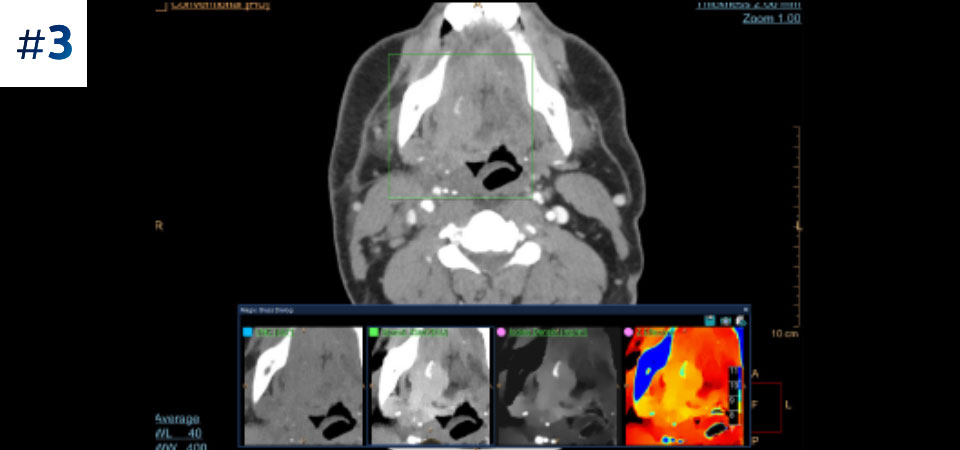

Masse au niveau du cou

Téléchargez les cas ici